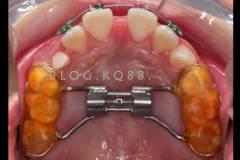

部分早期矯正裝置